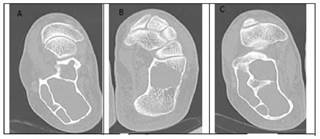

Our study involved the processing of bone CT images, so as to identify the region of bone cancer and perform a 3D evaluation. Axial raw CT images containing healthy and bone tumors are presented in Figures 2 and 3.

(A, B, C) axial CT slices of bone tumors

Figure 3: (A, B, C) axial CT slices of bone tumors

Source: Authors